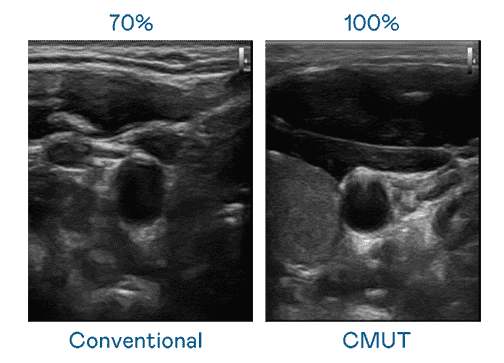

CMUT 技术是一种用电容式微机电元件来产生超音波讯号的技术。。与传统 PZT 压电式技术相比,,CMUT 频宽增加 30%,,,更宽频的超音波讯号让影像解析度大幅提升,,,是实现高影像品质医疗超音波扫描、、促进精准医疗发展的关键技术。。

超音波影像的解析度高低,,首先取决于探头能发出的讯号频宽。。。。尊龙集团 CMUT 可提供高清晰的超音波讯号,,,提供高频宽、、、、高灵敏度、、、影像纹理细节更高的超音波影像,,协助医护人员缩短影像判读时间及利用精准的医疗影像进行诊断。。。。